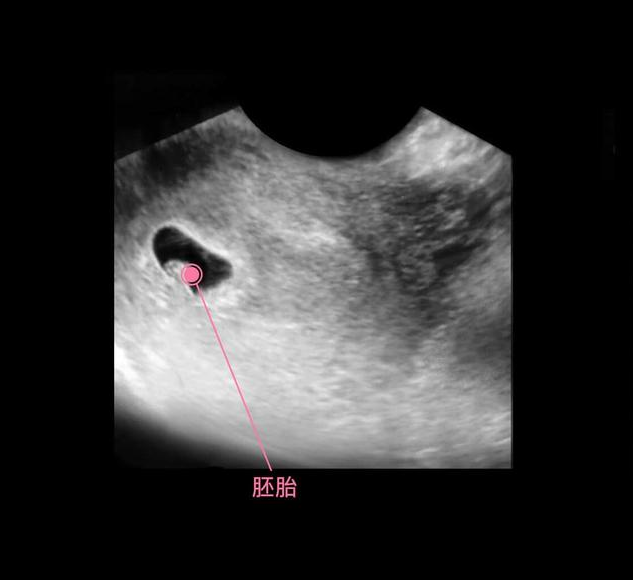

此时进入了第6周,胚胎已经具备了雏形,依稀可以卡到一个小人的形状,胚胎上下两面开始长出幼芽,将来发育成胎儿的手臂和小腿,面部器官开始形成雏形,不再是小海马的样子了。

在上图可见是个双胎妊娠,胎儿具有一个很大的头,和身材很不对称,是不是跟出生后的胎宝宝有点像了?其实此时的头部比例更悬殊,宝宝的额面部器官发育很明显,心脏也开始了跳动,出现了胎心,此时做B超,可见震了厘胎心胎芽。